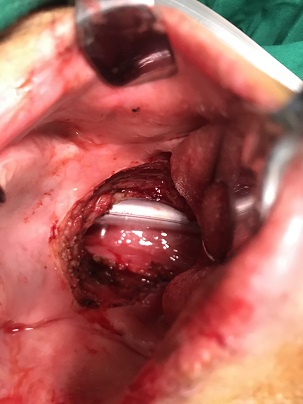

32 YEARS OLD MALE SUFFERING FROM RIGHT LOWER GINGIVO BUCCAL MUCOSA CARCINOMA INVOLVING RIGHT RETROMOLAR TRIGONE.PATIENT HAS ACTIVE PULMONARY TUBERCULOSIS.RIGHT RADICAL NECK DISSECTION WITH RIGHT DISTAL MANDIBULECTOMY WITH RIGHT LOWER ALVEOLECTOMY WITH RIGHT PECTORALIS MAJOR MYOCUTANEOUS FLAPE DONE.

31-12-2021